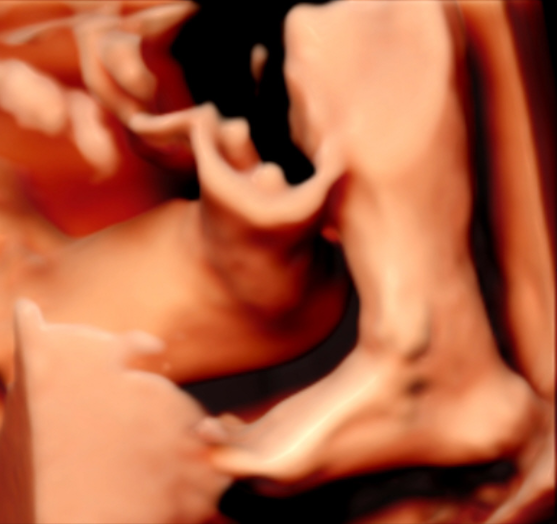

5D智能彩超拥有更高的分辨率和更强的图像处理能力,能够呈现出接近“IMAX电影画质”的细腻影像 。它采用一种被称为“水晶成像”的技术,能够穿透组织,将胎儿的骨骼、器官和组织结构以极其清晰、立体的形态展示出来。这种高清晰度对于观察胎儿微小的解剖结构细节至关重要,例如手指、脚趾、耳廓形态等,有助于医生发现一些在传统超声下不易察觉的细微异常,为排畸诊断提供了更丰富的视觉信息。

传统超声检查有时会因为胎儿体位、羊水量等因素的限制,导致某些部位观察不清。5D智能彩超技术能够实现对目标结构进行360°全方位、多切面的自由旋转观察。医生可以像“雕塑家”一样,从任意角度审视胎儿的解剖结构,尤其对于形态复杂的心脏、颅脑和脊柱等部位,这种能力可以极大弥补单一平面的局限性,帮助医生更全面地评估其发育状况。